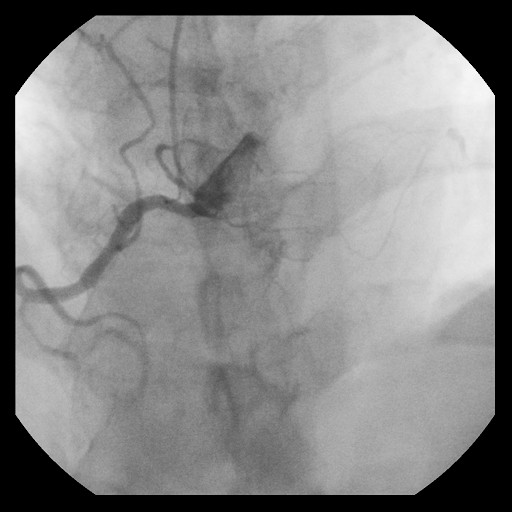

Re-attempted PCI for LAD CTO was planned. The procedure was performed with an 8-Fr, SPB 3.5 SH for the antegrade approach and a 6-Fr IMA for retrograde angiography. Primary antegrade approach was performed because there were no feasible collateral channels. Gaia Next 3 could penetrate the proximal cap of CTO. Since Gaia Next3 could not proceed into the CTO mid portion, the guide wire was escalated to Gaia Next 4. However, Gaia Next 4 advanced into extra plaque space beyond the CTO distal true lumen angiographically. Therefore, we decided to perform tip-detection (TD) method using intravascular ultrasound (IVUS). IVUS revealed that the guide wire proceeded into extra plaque from the CTO proximal portion, although the CTO entry was in the intra plaque space. At first, we tried TD-intra plaque tracking (IPT) in the CTO body. However, Conquest Pro 12 ST (CP-12ST) could not penetrate the CTO body. Therefore, we performed TD-antegrade dissection andreentry (ADR). Eventually, CP12 ST succeeded to puncture the distal true lumen supported by a Caravel. We implanted a drug-eluting stent, which resulted in successful revascularization.